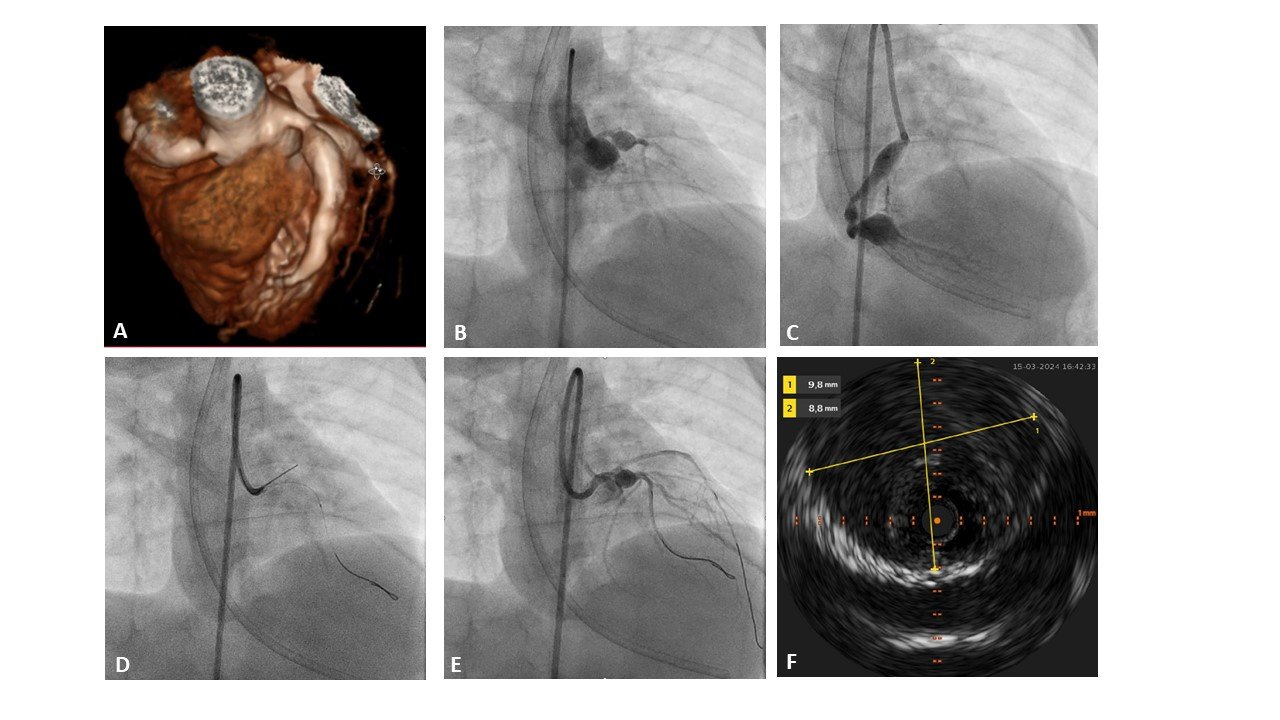

Introduction – 9-month-old infant (9 kg) with a history of a delayed diagnosis of Kawasaki disease with major coronary artery aneurysms of the left and right coronary artery (Figure A-C), was admitted to the PICU for systemic fibrinolysis. This was due to a large thrombus in the aneurysm of the proximal LAD, despite being on triple anticoagulation therapy (ASA, clopidogrel, low-molecular weight heparin). The initial systemic treatment was largely successful in resolving the thrombus. However, after two weeks, signs of acute ischemia emerged (ECG changes and elevated cardiac enzymes). Echocardiography and CT-A suggested a possible complete occlusion of the LAD.

Methods and Results – The infant was transferred to the catheterization laboratory for further diagnostics and percutaneous coronary intervention. Angiography confirmed occlusion of the proximal LAD by a large thrombus, with no collateral supply of the distal LAD (Figure B). Due to the child’s small size, it was not possible to safely position a 5Fr guiding catheter in the ostium of the left main coronary artery, so it was left in the left coronary cusp. Subsequently, coronary balloon angioplasty with 1.5 mm and 2 mm coronary balloons was performed, resulting in revascularization of the LAD (Figure D-E). Endovascular ultrasound (IVUS) revealed large thrombus burden in the aneurysmatic segments of the proximal LAD (Figure F). Stents were not implanted given the small size of the non-diseased coronary artery system, the risk of stent thrombosis and at later stage possible stent malposition. By restoring antegrade flow in LAD anticoagulants and interleukin-inhibitor therapy for Kawasaki disease was more effective. In the following days the child’s condition improved, with normalization of the ECG and cardiac enzymes. Surveillance imaging (CT-A and echocardiography) confirmed the patency of the LAD.